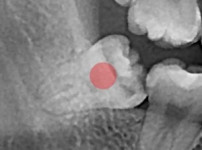

严重龋坏的智齿